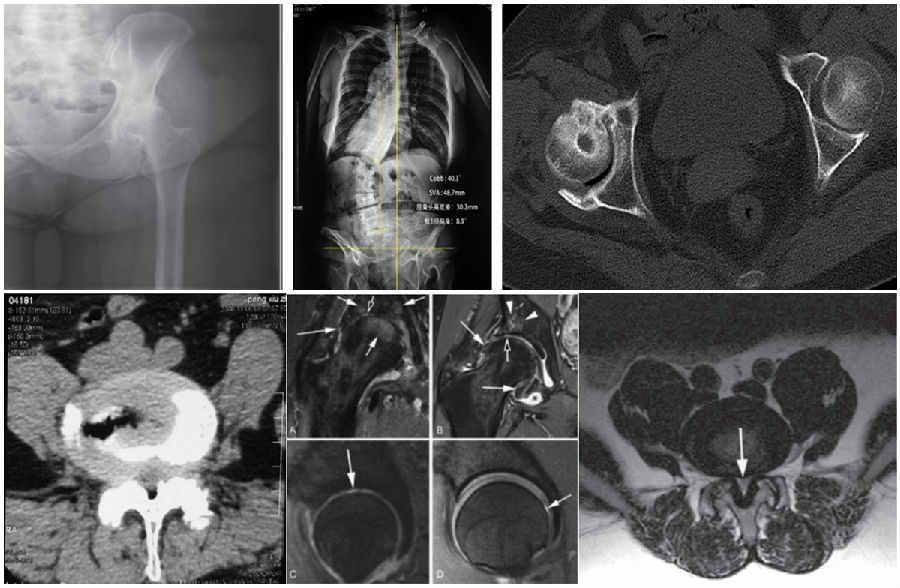

• Case 2(湘雅二医院)

-王某某,男,79岁, 反复腰痛8年

- 8月前出现右侧髋外侧明显疼痛,活动受限,伴左侧臀部疼痛并放射至大腿、小腿外侧至足背

-既往史:冠心病, 糖尿病, 脑梗,尿毒症

-体查:脊柱S型侧弯,双下肢感觉减退,右髋关节“4”字征(+),左侧直腿抬高及加强试验(+)

-治疗:先做THA,术后3月左下肢症状加重,不能行走,行局麻下孔镜翻修

- 刘某某,女,63岁,脊柱后凸并腰痛20年

- 2年前加重并出现双侧臀部疼痛,沿双侧大腿外侧放射至膝关节,右侧为甚,并间歇性跛行及双下肢麻木感。

- 查体:脊柱S型侧弯,腰椎后凸,双下肢感觉减退,右髋关节活动明显受限,右侧直腿抬高及加强试验(+),双侧4字征(+),双侧托马斯征(+)。

- 腰椎退变性侧凸合并髋关节OA

- 手术:腰椎减压、长节段矫形融合术,2年后右侧THA,随后1年再行左侧THA,右髋随访2年松动进行翻修